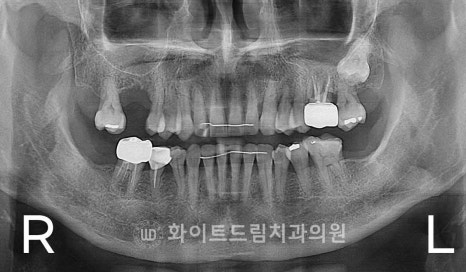

[동일 인물이며 동일 환경에서 촬영됨 / 강남역어금니임플란트 : 23.04.04 - 23.09.27]

오늘 준비한 케이스도 이런 문제로 인해 16번 치아를 발치하신 뒤

방치를 하셔서 결국 잇몸 함몰까지 나타난 상태로 내원을 하셨던 환자분인데요.

상악동이 크게 내려온 경우는 아니었지만,

발치 후 협측 피질골(buccal cortical bone) 이 얇아지고 일부 흡수되면서

잇몸 볼륨이 부족해진 상태였습니다.

환자분의 경우 남아있는 잔존 잇몸뼈(치조골)의 높이가 약 3~4 mm 정도로 매우 낮아,

임플란트를 심을 경우 임플란트가 상악동 내부로 돌출될 위험이 있었습니다.